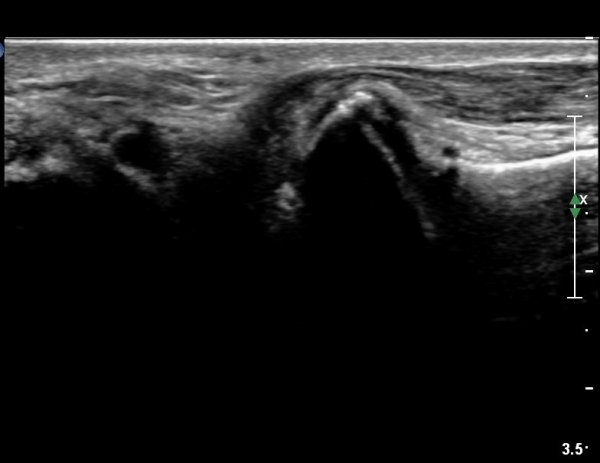

Sinus tarsi Á¾´Ü¸é, Ⱦ´Ü¸é°Ë»ç¿¡¼­ sinus tarsi ³» ºÎÁ¾À» º¸ÀÓ(»çÁø 5, 6).